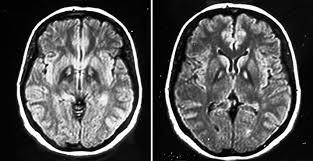

MRI features symmetric WM hyperintensities, including in anterior temporal poles